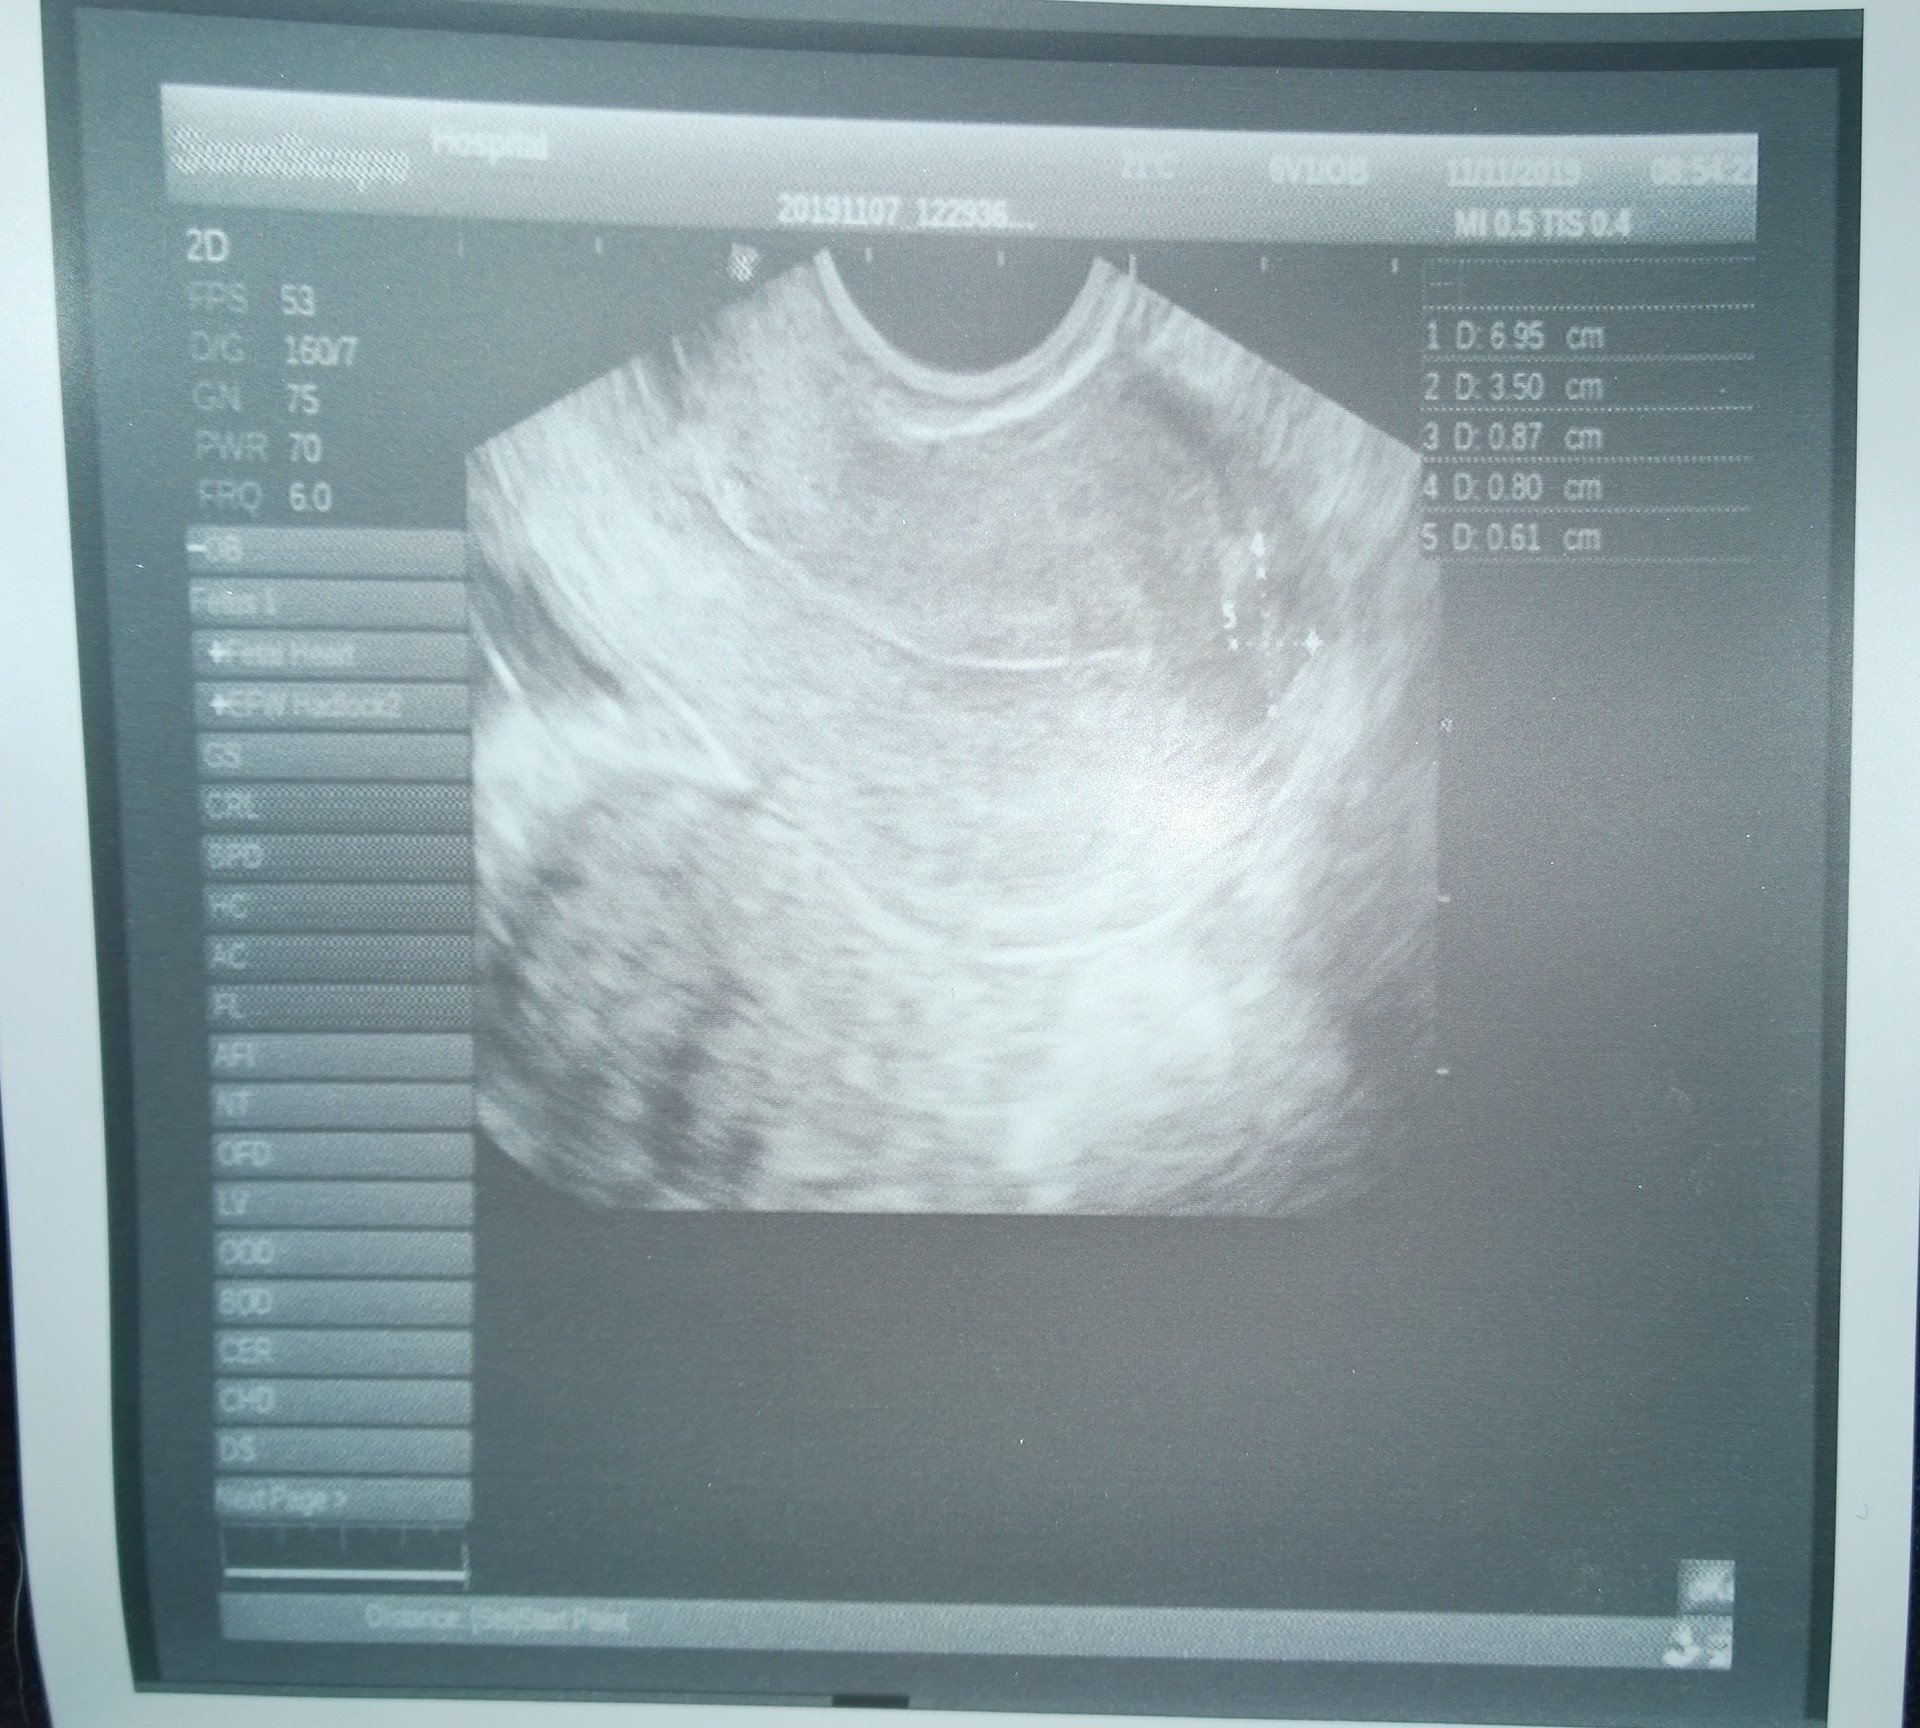

Хистероскопията е процедура, която включва директен оглед на маточната кухина с помощта на оптична система и осветление. Прилага се както за диагностични, така и за терапевтични цели при различни гинекологични състояния, като прекомерни или продължителни менструации, междуменструално кървене, нередовни менструални цикли, безплодие, съмнение за неправилно поставена вътрематочна спирала , съмнение за вродени маточни аномалии, съмнение за сраствания в маточната кухина и други. Хистероскопията е процедура, която включва използването на хистероскоп за изследване на вътрешността на матката. Извършва се с цел диагностициране и лечение на състояния като полипи, хиперплазия на ендометриума, рецидивиращи полипи и други проблеми, които могат да доведат до трудности при забременяване.